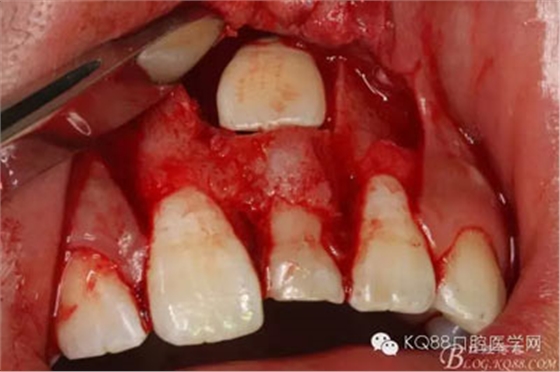

圖12.摘除囊壁后,暴露出21的切端

圖13.超聲骨刀清理周圍組織,21有Ⅰ°松動

圖14.牙冠周圍滲血多,無法粘結(jié)托槽。位置也高,隨與家屬溝通,暫時保留乳Ⅰ。待21初步穩(wěn)定,再考慮正畸牽引